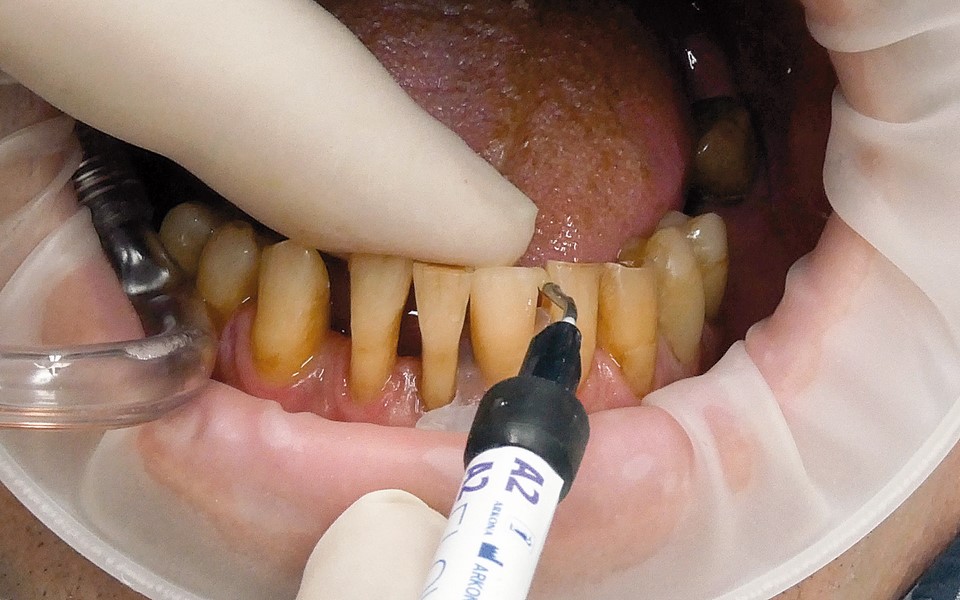

Jedną z popularniejszych metod stabilizacji zębów rozchwianych jest ich szynowanie. Metoda ta, wspierająca inne metody leczenia, jest powszechnie stosowana. Jednym z najnowocześniejszych materiałów wykorzystywanych w stomatologii do szynowania zębów jest taśma poliaramidowa. W opisanym przypadku autorzy pracy przedstawiają sposób uproszczenia całej procedury i ograniczenia ryzyka popełnienia błędu, szczególnie w sytuacji całkowitej utraty zęba. Uzyskano to dzięki zastosowaniu indeksu wykonanego z przezroczystego silikonu.

One of the more popular methods of stabilising loose teeth is to splint them. This method, aiding other methods of treatment, is generally used. One of the most modern materials used in dentistry for splinting teeth, is polyamide tape. In the case described the authors show how to simplify the whole procedure and limit the risk of making a mistake, particularly in the situation of total loss of one tooth. This was achieved thanks to the use of an index made out of transparent silicone.